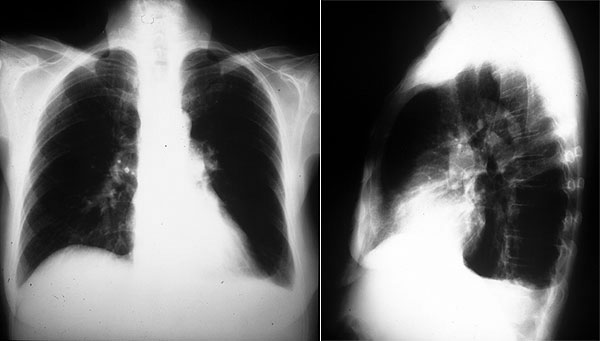

Placa 41 / Placa 42